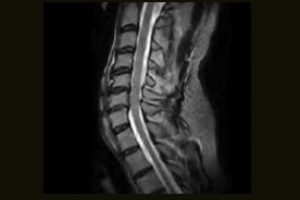

Clinical Images

Immediate access to high quality MR images can help your practice achieve new levels of efficiency and patient satisfaction. From C-spine anomalies to foot injuries, the S-scan dedicated MRI system efficiently delivers a range of MSK MRI studies within your existing practice.

Comprehensive MSK Imaging